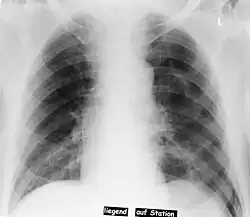

Deep sulcus sign

| Pneumothorax left sided | |

| Differential diagnosis | pneumothorax |

In radiology, the deep sulcus sign on a supine chest radiograph is an indirect indicator of a pneumothorax.[1][2] In a supine film, it appears as a deep, lucent, ipsilateral costophrenic angle[3] within the nondependent portions of the pleural space as opposed to the apex (of the lung) when the patient is upright. The costophrenic angle is abnormally deepened when the pleural air collects laterally, producing the deep sulcus sign.[4]

Patients with chronic obstructive pulmonary disease (COPD) may exhibit deepened lateral costophrenic angles due to hyperinflation of the lungs and cause a false deep sulcus sign.[4]